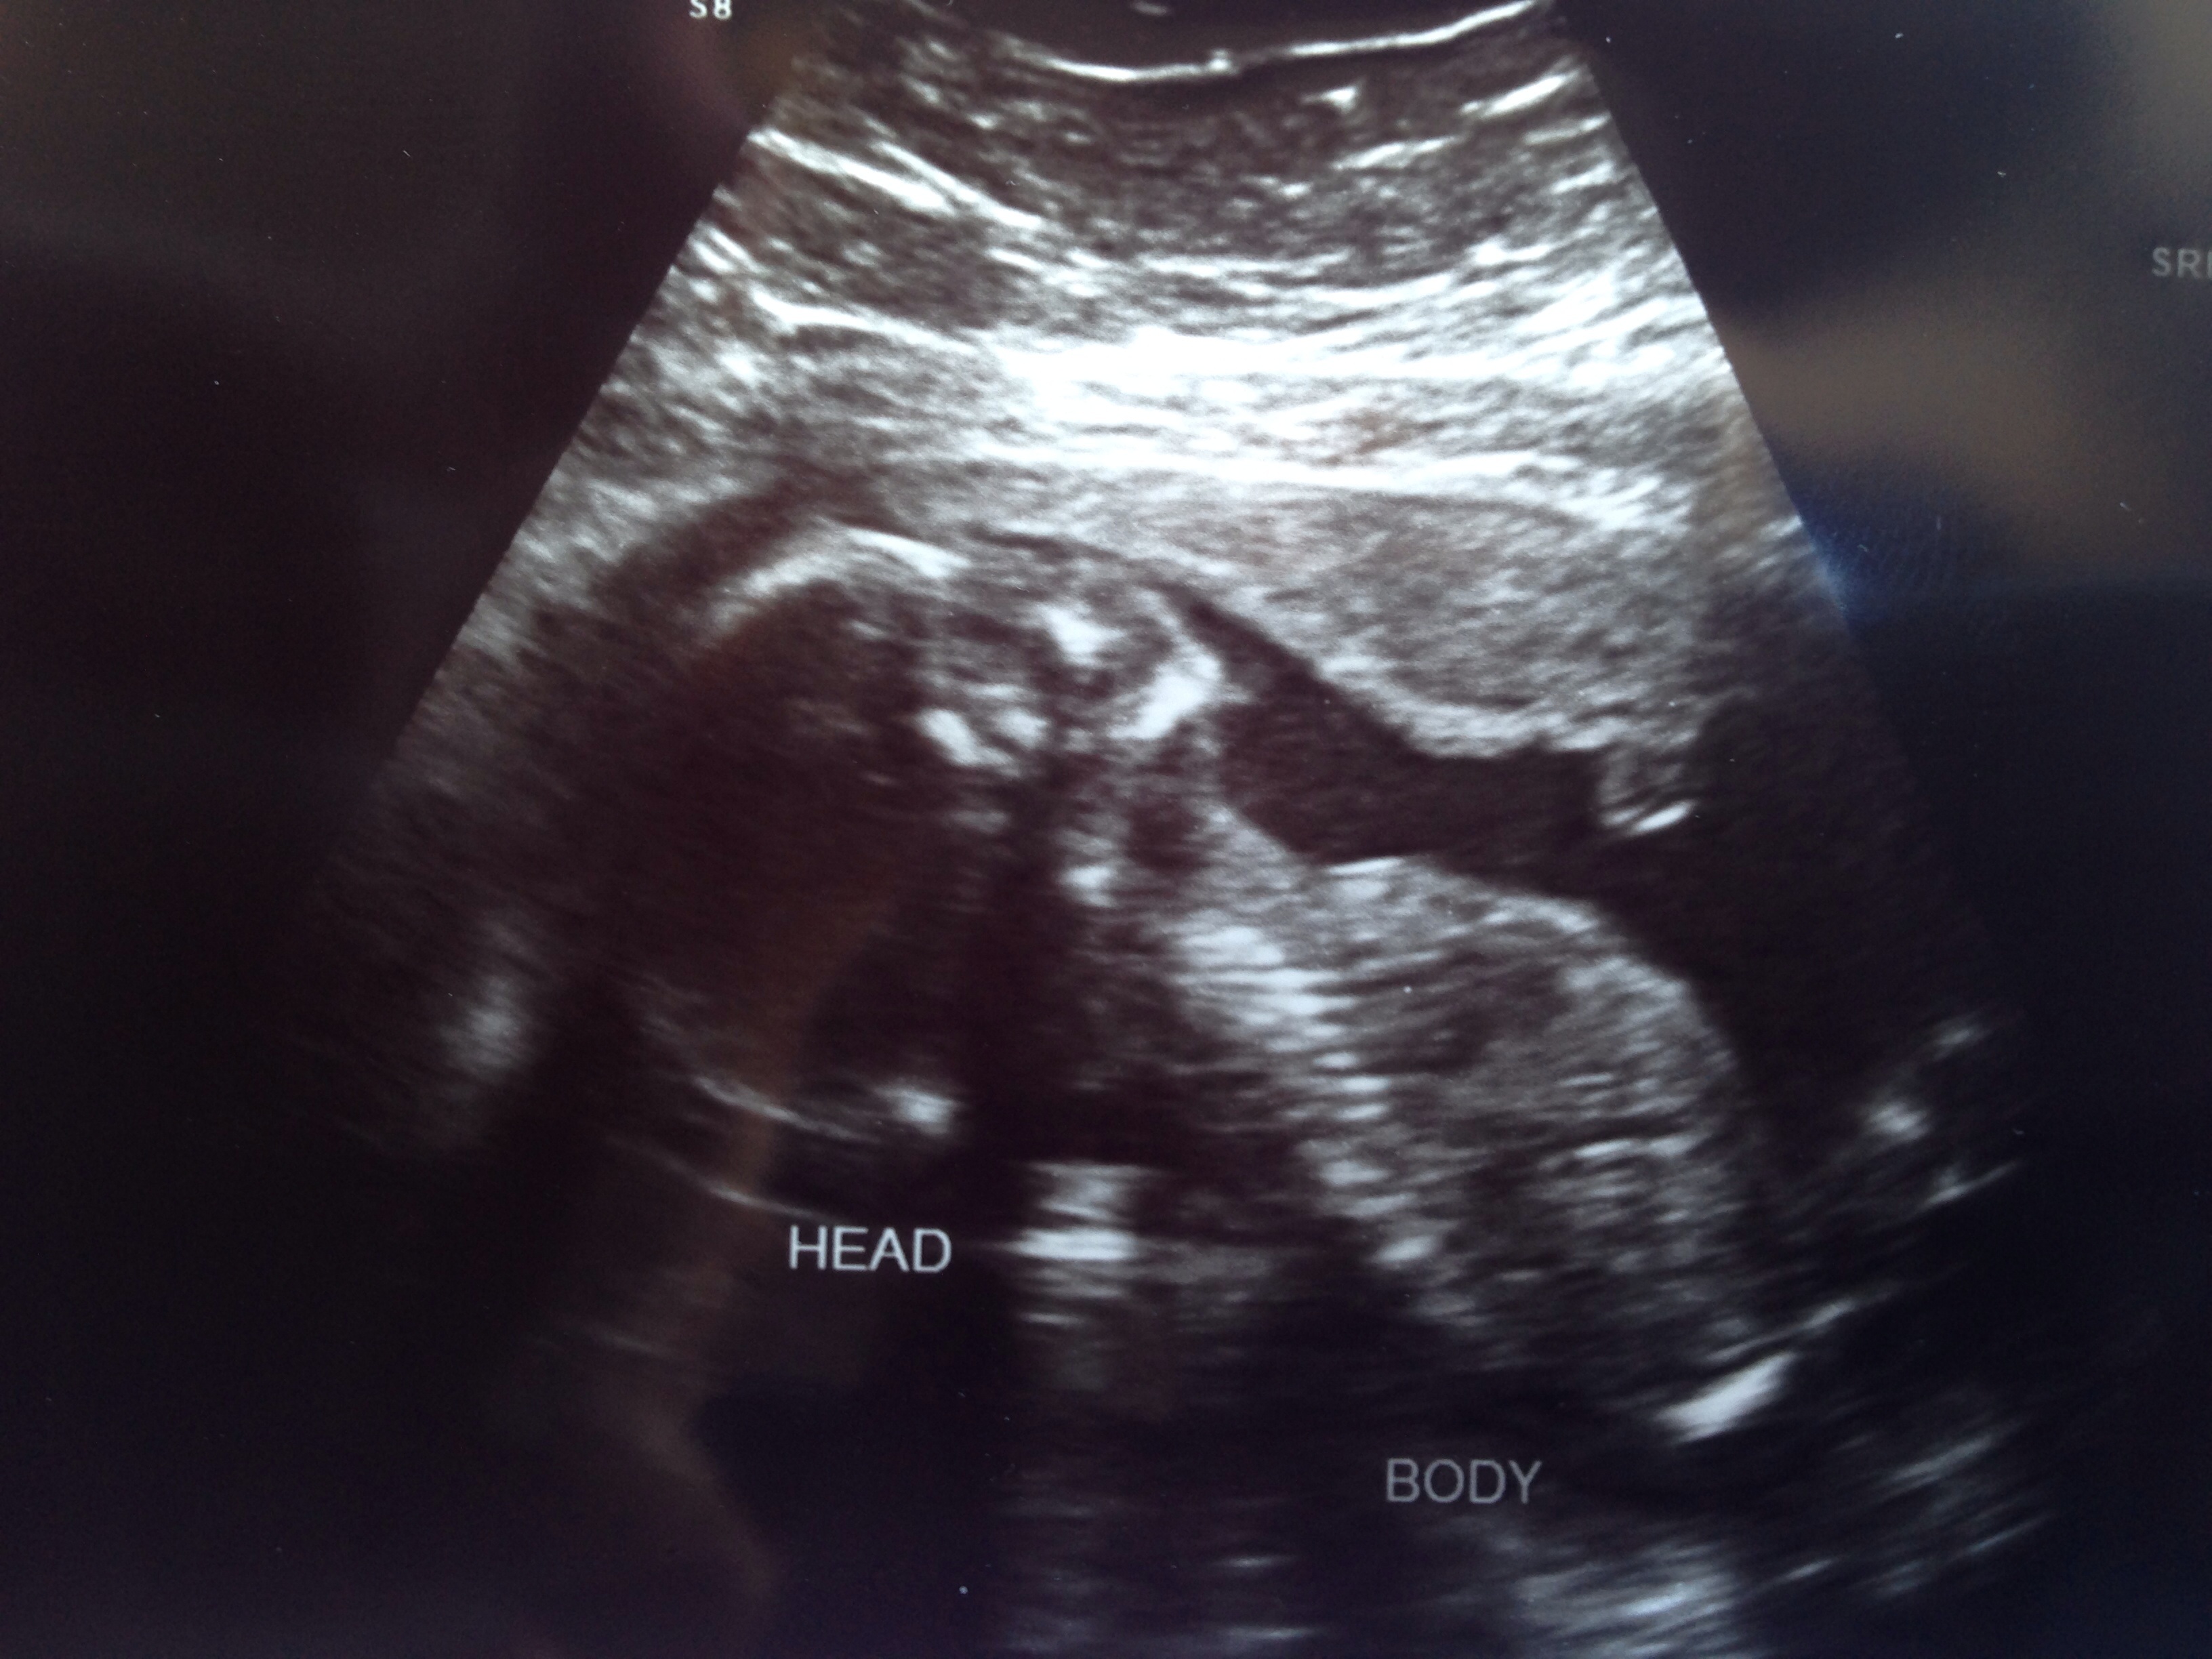

Sorry it's a little late (was busy today). We had A/S today, although we had u/s tech seal it in an envelope. We are finding out gender on Saturday at our reveal party. :-) otherwise baby is doing great. Everything looks and measures good.